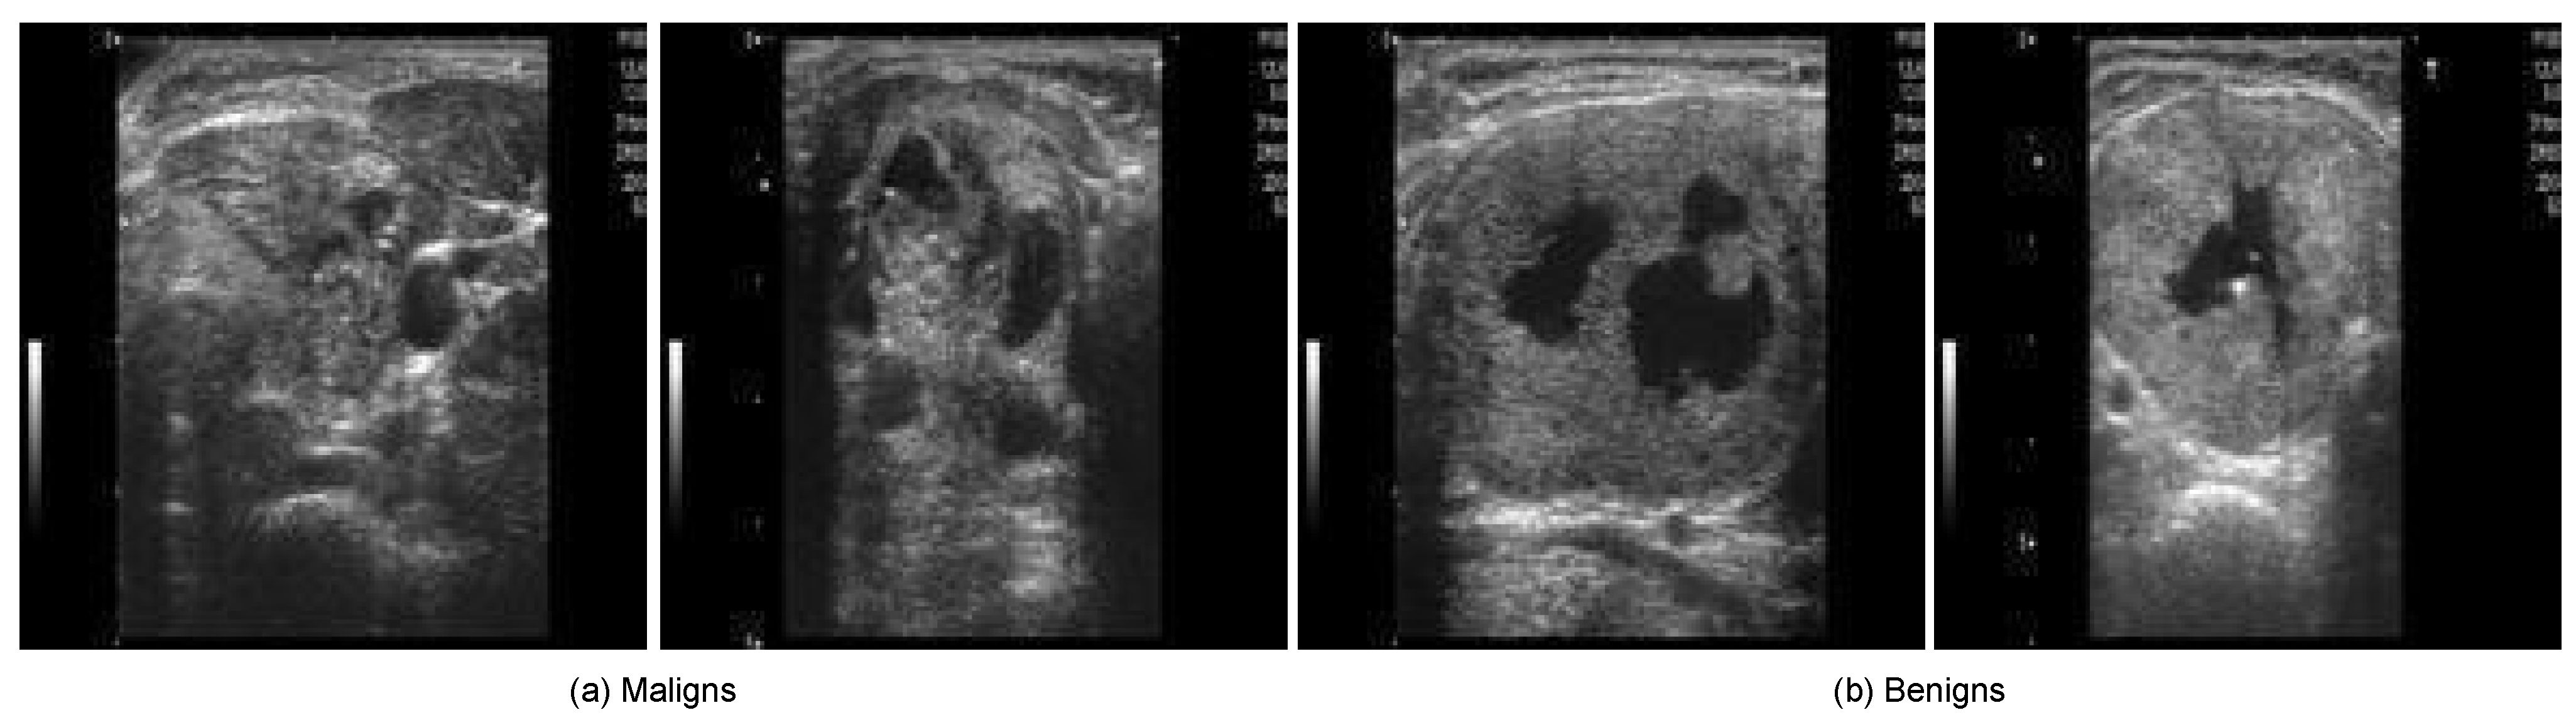

4.1. Input TC Datasets

| Image Modality | B-mode 2D greyscale US |